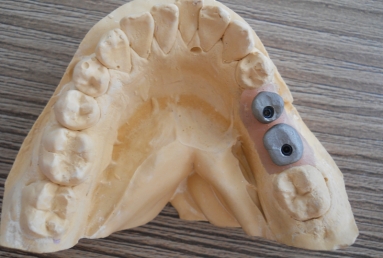

Initial situation: two missing teeth, second lower premolar and first lower molar. two dental implant are integrating in the mandibular bone for 4 months, then, gingival healing caps are applied for 3 weeks. an impression is taken for the dental lab in order to manufacture 2 porcelain fused to metal crowns. they will be screwed directly in the implant body.